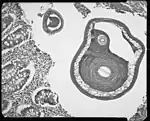

Trichuris trichiura, ou Trichocephalus trichiuris, est une espèce de nématodes (les nématodes sont un embranchement de vers non segmentés, recouverts d'une épaisse cuticule et menant une vie libre ou parasitaire). C'est l'un des parasites du tube digestif humain, dont des œufs fossilisés sont encore trouvés sur des lieux de fouilles archéologiques préhistoriques[1].

C’est un nématode de 3 à 5 cm de long.